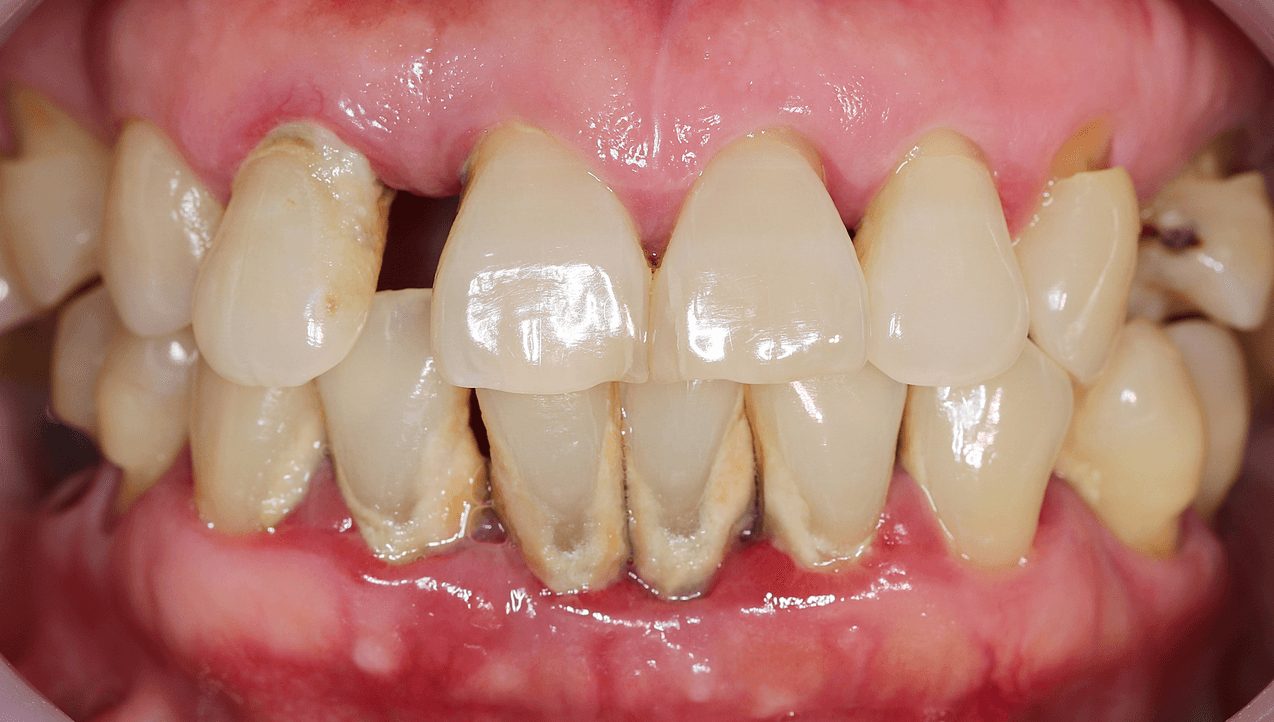

2) Viêm nha chu - tụt nướu - tiêu xương ổ răng

Vôi răng dưới nướu là yếu tố kích thích viêm nha chu tiến triển, phá hủy mô nâng đỡ răng (nướu, dây chằng nha chu, xương ổ răng).

Hậu quả cuối cùng:

- Nướu tụt

- Chân răng lộ ra ngoài

- Răng lung lay và có nguy cơ mất răng sớm

Vôi răng lâu ngày làm tụt nướu, viêm nướu